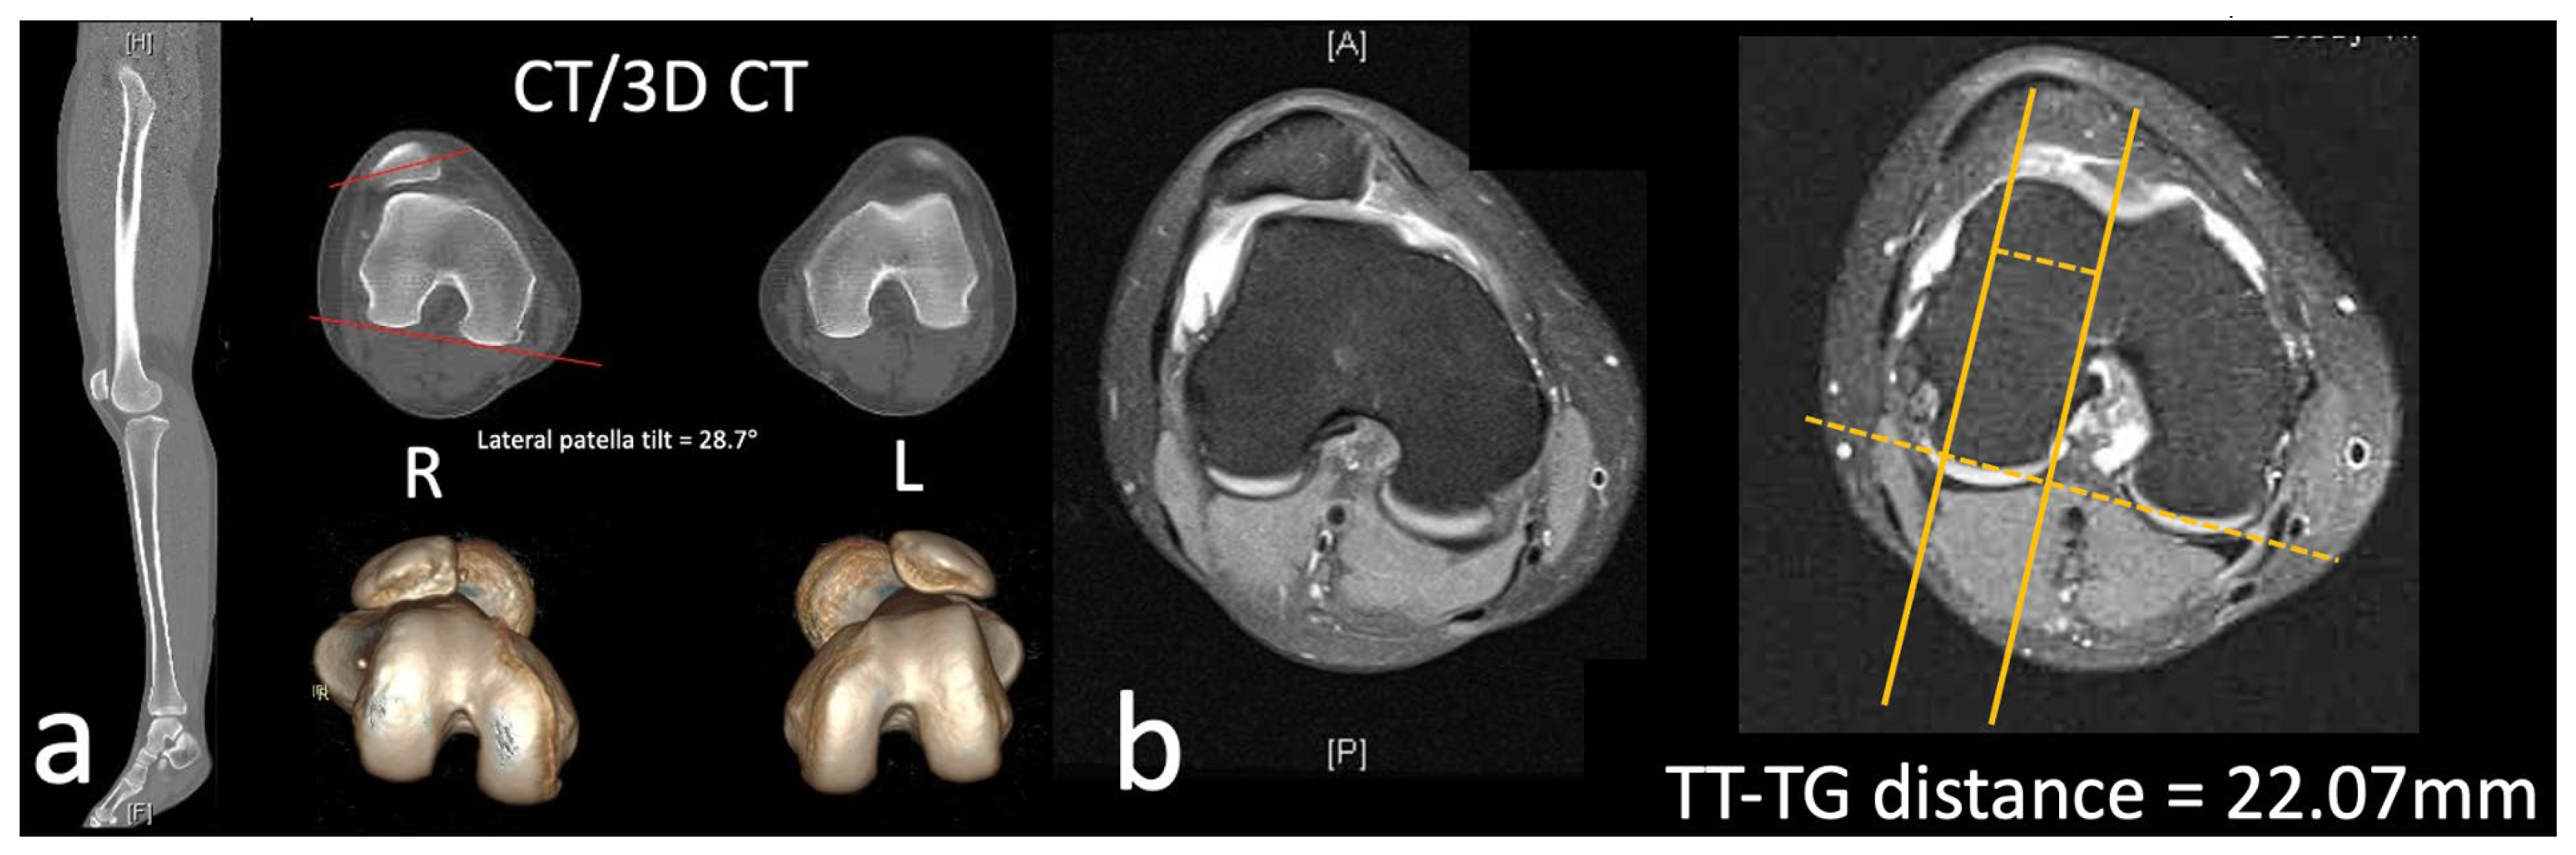

2. Clinical Cases

2.1. Case

3.3. TT–TG Distance